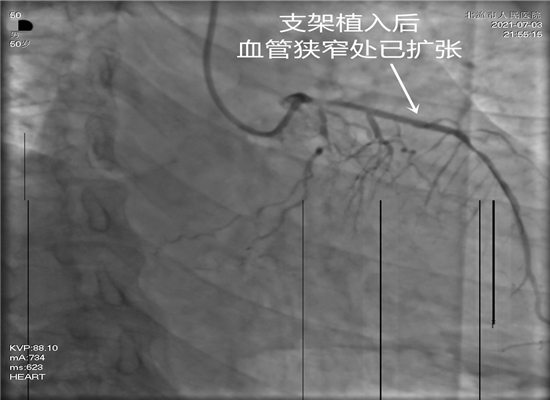

时间就是生命,这是一场与死神生死竞速的硬仗。21时15分,病人进入导管室,在赵子粼博士的主持下,张轩副主任亲自操刀,介入团队密切配合,快速穿刺桡动脉、置管、造影,升压,开通闭塞血管,植入支架。经过约50分钟的全力救治,成功挽救了患者的生命。目前,术后患者症状明显改善,恢复较好。

相关连接介绍:近年来,介入手术在我院已成功开展近1400例。据赵子粼博士介绍,急诊PCI手术,是指患者发生急性心肌梗死后12小时内进行的冠状动脉血运重建,患者首先在心脏导管室行冠状动脉造影术,找出冠状动脉病变血管及病变部位,对病变部位行经皮冠状动脉腔内成形术和植入支架,使闭塞的血管得以再通,梗死的相关心肌得以及早的再灌注和功能恢复。这是一项恢复冠状动脉血流最直接、最有效的治疗法之一,具有冠状动脉通畅迅速,残余狭窄轻和近、远期预后佳等优点,对减少心肌梗死的并发症,提高存活率、降低病死率和致残率都有重要意义。